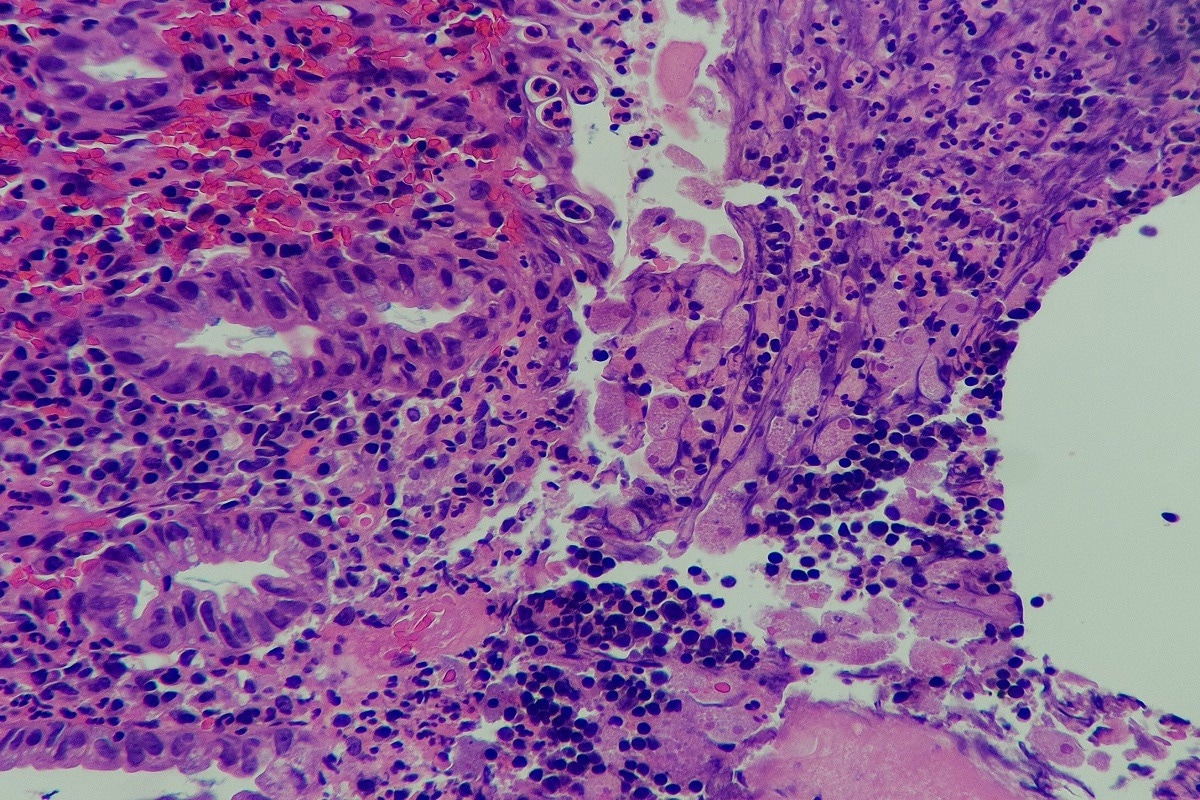

Colonoscopy and microscopic examination of biopsies are the gold standards for diagnosing amoebic colitis. The trophozoite contained within ulcers can be seen under a microscope. Patients with diarrhea are likely to have E. histolytica present in the stool. As the cecum and ascending colon are affected, histological examination of the ulcers shows flask-shaped protozoa. in severe cases, the ulcers will merge and present as ulcerative colitis.